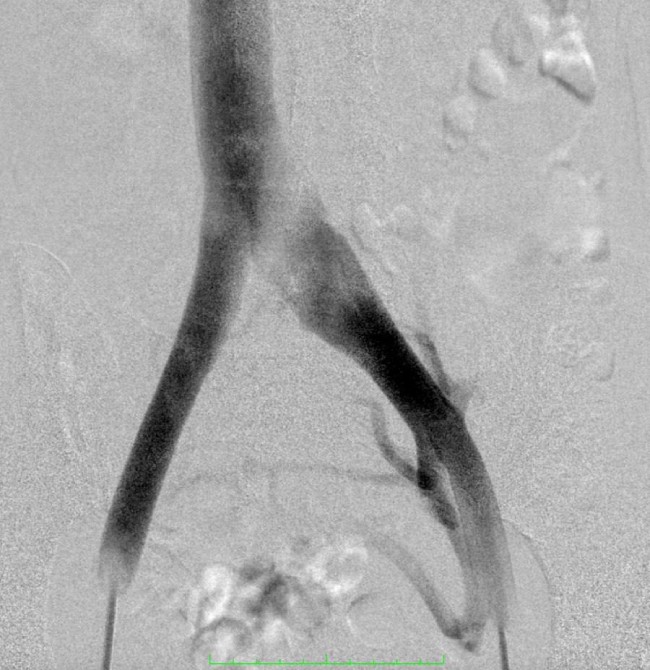

- Флебография. Для визуализации венозной системы внутривенно вводят контраст, а затем делают серию рентгеновских снимков. Метод позволяет изучить градиент давления в вене, определить расположение и степень стеноза.